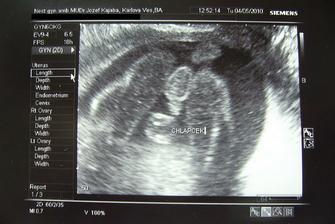

♥ 08.04.2010 Vyzerá to tak, že asi čakáme vytúženého chlapčeka :oD

♥ 04.05.2010 sme boli na bežnej poradni a všetko je ok. Dokonca naše milované chlapčiatko videl aj MM. Na ďalšiu poradňu ideme o tri týždne a dovtedy musíme stihnúť kopec vyšetrení